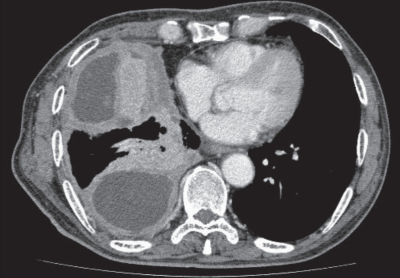

体温36.3 ℃。脈拍 72/分、整。血圧 128/72 mmHg。呼吸数 18/分。SpO₂ 98 %(room air)。右胸部の呼吸音は減弱し、打診で濁音を認める。血液検査所見で炎症所見は認めないが、胸水中のヒアルロン酸は 125,000 ng/mL と著明な増加を認めた。胸部エックス線写真と胸部造影 CTを別に示す。